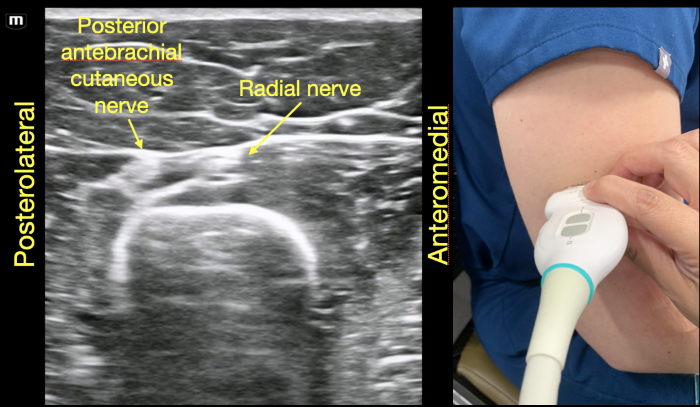

In this context, the mid-humerus shaft is not just an arbitrary location in the arm's anatomy; it holds strategic significance. The radial nerve, the largest nerve in the upper extremity, arises from the posterior cord of the brachial plexus. From the axilla, it traverses along the posterior aspect of the humerus through the cubital fossa, continuing along the dorsal aspect of the forearm, where it bifurcates into the superficial and deep branches.8 When the radial nerve is along the posterior compartment of the arm, it remains relatively superficial and identifiable at the mid-humerus level, making it a prime spot for reproducible identification and possible anesthetic placement. On ultrasound evaluation, the radial nerve will appear as a honeycombed structure superimposed on the humeral cortex which is obvious as a hyperechoic structure with posterior shadowing. (Figure 1) If the same orientation is maintained while sliding the probe distally the radial nerve begins to branch with the deep branch extending between the brachioradialis and brachialis muscles. (Figure 5) We suggest that recognizing the radial nerve in the mid-humeral position may ensure a higher success rate for the UGRA procedure regardless of the final desired position for injection as it allows for easy identification of the radial nerve branches as the probe is moved distally along the arm. In the mid-humerus position, the radial nerve is within a deep fascial plane accompanied only by the profunda brachii artery that is adjacent to it. If the UGRA is performed here, careful injection into the fascial plane will assist in reducing the risk of arterial infiltration or injury. It is recommended to use an in-plane needle technique regardless of the final position chosen for injection for full needle visualization.

To identify the radial nerve in the mid-humerus position, have the patient in a seated position with the arm extended or held over the abdomen with the elbow flexed. Start with the probe placed transverse across the posterolateral mid-humerus and identify the radial nerve as a hyperechoic honeycombed structure lying directly on top of the humerus. At this point the radial nerve lies within the spiral groove and is also seen adjacent to the deep brachial artery. (Figure 7A)

RadialNerve-Image1 Aug2024.pngFigure 1. Radial nerve lying directly on top of the mid-humerus adjacent to the deep brachial artery.